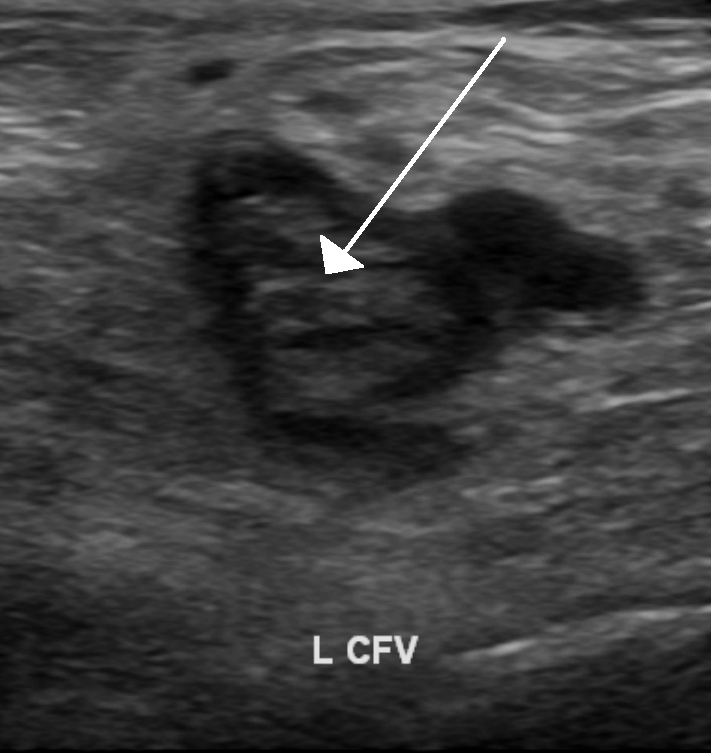

What's the Diagnosis?